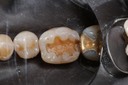

Matt Dodson #3 reprep